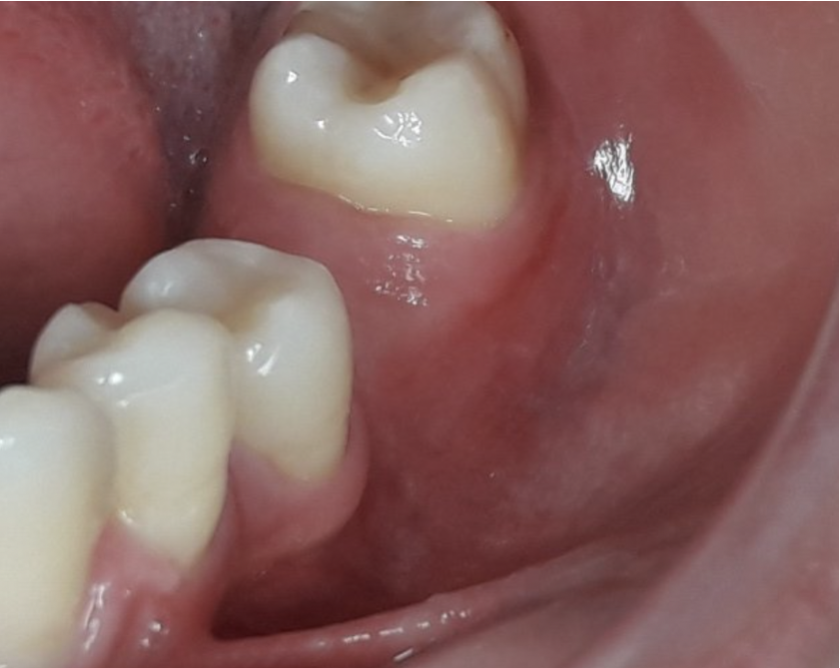

La perdita di un elemento dentario esita spesso in un deficit volumetrico dei tessuti duri e molli del mascellare, in particolare sul suo versante buccale. Le conseguenze oltre che di carattere estetico sono spesso di carattere funzionale (ristagno di cibo e placca al di sotto della protesi) che in alcuni casi possono compromettere il successo a lungo termine delle riabilitazioni impianto protesiche.

Nello studio sono stati inclusi 20 pazienti (12 donne e 8 uomini) di età compresa tra i 28 e i 65 anni, con edentulia singola e conseguente deficit vestibolare dei tessuti molli. La matrice dermica a elevata consistenza è stata opportunamente ritagliata mediante forbici e lama ed è stata posizionata al di sotto del lembo muco periostale allestito con approccio a spessore totale, vestibolarmente alla cresta ossea in cui è stato posizionato contestualmente un impianto endosseo osteointegrabile. Non si è utilizzato alcun ausilio di fissazione per la matrice dermica che è stata stabilizzata dal solo lembo di accesso ribaltato su di essa e suturato, mediante punti staccati semplici, al lembo linguale.

Le rilevazioni eseguite a distanza di 18 mesi di tempo medio, hanno mostrato un netto miglioramento del PES (Pink Esthetic Score) con un punteggio medio superiore a 9 (eccellente) e in due casi un punteggio tra 6 e 8 (buono). La sovrapposizione dei file .stl provenienti dalla scansione della arcata dentaria interessata prima dell’intervento e a distanza di 18 mesi ha permesso di rilevare un incremento medio in senso orizzontale di 2 mm in media.